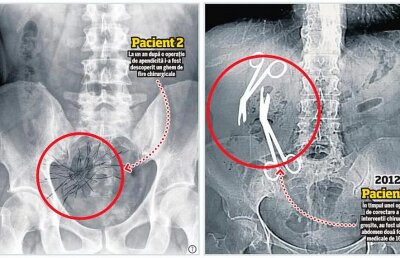

INVESTIGAȚIE EXCLUSIVĂ/ Chirurgul Gheorghe Ștefan lovește din nou! După foarfeci, a uitat și "un ghem" de ațe într-un alt pacient!

INVESTIGAȚIE Libertatea / Directorul medical al Spitalului Militar din Constanța a uitat două foarfeci de 16 cm în burta unei paciente de 61 de ani!